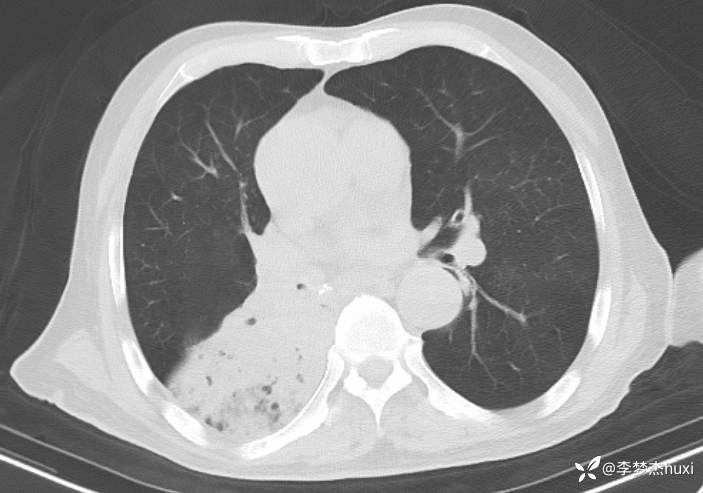

【现病史及既往史】: 1.患者老年 男,患者缘于3小时前无诱因出现意识不清,伴咳嗽、咳痰,痰不易咳出,伴发热,最高体温不详,院外应用“退热药物”(具体不详)治疗,无恶心、呕吐,无大小便失禁,无胸痛,今为求进一步治疗来院就诊,急诊查胸部及头CT:双侧基底节区腔隙性脑梗塞,脑白质稀疏,脑萎缩,脑干密度不均匀,右肺感染首为考虑,占位待除外,建议治疗后复查,右肺中叶局限性炎症,双肺间质性改变,主动脉及冠状动脉钙化,双肺气肿,左肺实性结节,建议复查,纵隔内及右肺门结节,右肺门增大。右肺下叶部分支气管堵塞。右侧胸膜局部增厚并少量积液,甲状腺密度不均匀,胆囊结石,右肾类圆形囊性密度影,建议结合超声。查血常规:白细胞数目 13.91*109/L,BNP前体 1360pg/ml。D-二聚体 0.8pg/ml。以“肺炎”收住院;。

4.辅助检查:急诊查胸部及头CT:双侧基底节区腔隙性脑梗塞,脑白质稀疏,脑萎缩,脑干密度不均匀,右肺感染首为考虑,占位待除外,建议治疗后复查,右肺中叶局限性炎症,双肺间质性改变,主动脉及冠状动脉钙化,双肺气肿,左肺实性结节,建议复查,纵隔内及右肺门结节,右肺门增大。右肺下叶部分支气管堵塞。右侧胸膜局部增厚并少量积液,甲状腺密度不均匀,胆囊结石,右肾类圆形囊性密度影,建议结合超声。查血常规:白细胞数目 13.91*109/L,BNP前体 1360pg/ml。D-二聚体 0.8pg/ml。。